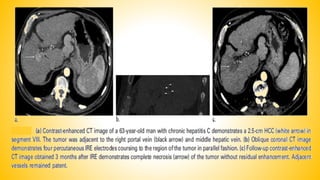

Follow up after the procedure

• Following completion of the IRE treatment, we perform a post

procedure CT scan the same day or the following day to evaluate for

any immediate complications and to evaluate if the lesion has been

entirely treated. Contrast is administered if renal function permits.

• Successful treatment is signified by a lack of contrast enhancement in

the ablation zone and complete coverage of the lesion by the ablation

zone.